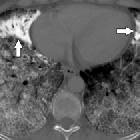

CT

HRCT better shows numerous sand-like calcifications throughout the lungs with subpleural and peribronchial distribution (typically ~1 mm) . Additional accompanying HRCT features include

- crazy paving pattern

- calcified interlobular septa (virtually pathognomonic)

- small subpleural cysts/emphysema

- black pleura sign

- ground glass opacities: tends to be more common in children